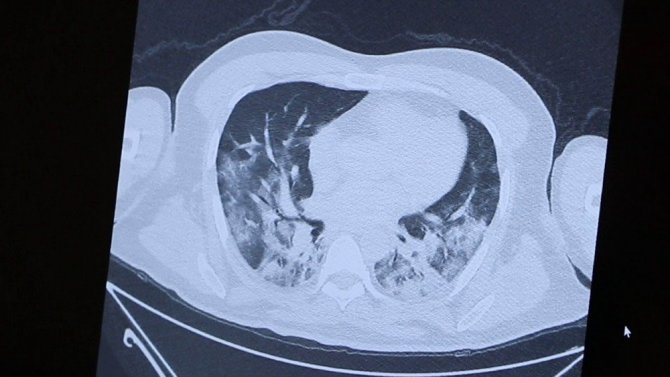

"Ölümden kıl payı kurtulan bir doktorun akciğerleri"

Önce sağlık çalışanlarının aşılanacağını belirten Prof. Dr. Özkaya, "Doğrusunu söylemek gerekirse bu incelediğimiz tomografi, ölümden kıl payı kurtulan bir doktor arkadaşımın tomografisi. Gördüğünüz gibi kendisi canla başla Kovid-19 hastalarını tedavi ederken hastalığa yakalandı. Günlerce hayati tehlike yaşadı. Önce sağlık çalışanlarını aşılayacağız çünkü sağlıkçılar ne kadar güçlü olursa toplumun da o kadar güçlü olacağını düşünüyoruz. Bu görüntüsünü gördüğünüz film de 40'lı yaşlarda bir hastamızın akciğer filmi. Gördüğünüz gibi yaygın bir akciğer tutulumu var. Biz normalde 65 yaş üstünü sokağa çıkmayı yasaklıyoruz ama gördüğünüz gibi 40'lı yaşlarda da çok ciddi akciğer tutulumuyla gelen hastalar oluyor. Bu da bugün kontrole gelen akciğeri pırıl pırıl olan bir hastamız. Herkes bu kadar şanslı olmuyor. Bildiğiniz gibi 65 yaş üstü vatandaşlarımızı bu salgında çok fazla kaybettik. Onlar şu an hala evde hapisler. Toplumda ne kadar çok kişi aşılanırsa bu esaretten kurtulacağımızı düşünüyoruz" ifadelerini kullandı.